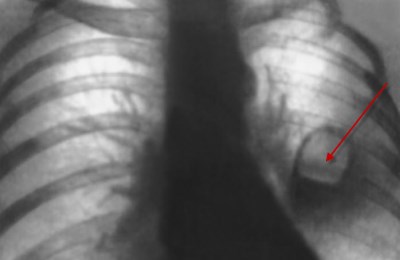

Механическое повреждение тканей дыхательных путей – это может быть повреждение от попадания инородных тел, последствие проведенной накануне бронхоскопии.

Также появление крови в горле характерно для ранений с повреждением дыхательных путей, нанесенных при помощи холодного или огнестрельного оружия.

Появляться кровь также может после значительной силы ударов в грудную клетку, а также при повреждении легких при переломе ребер.